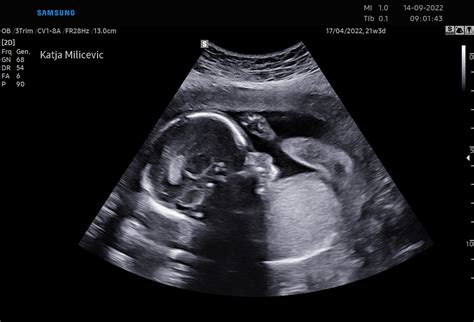

Trenutno si v zadnjem tednu četrtega meseca nosečnosti. V 17. tednu je otrokov obraz oblikovan skoraj v celoti. Na glavi je vedno več puhastih las, rastejo nežne trepalnice in obrvi. Otrok zdaj že lahko voha, sliši in okusi. Razvoj njegovih senzoričnih celic na različnih delih telesa pomeni, da je občutljiv na okolico in počasi že zaznava stvari. Zaradi povečanega zaznavanja in zavedanja se lahko ustraši glasnih zvokov - če boste v tem času imeli ultrazvočni pregled, boste lahko videli, kako njegovo telesce trzne. V 17. tednu nosečnosti lahko otrok že zaznava tudi svetlobo in temo, na primer, ko sonce sije na vaš trebuh.

Spol dojenčka: Kaj kmalu vas čaka veliki ultrazvok, na katerem boste izvedeli dojenčkov spol (če ga še ne poznate). Odločite se, ali želite že vnaprej vedeti, katerega spola bo dojenček, ki ga nosite pod srcem. Na prihodnjih pregledih boste vprašali za spol, kako mu ali ji bosta dala ime, v kateri porodnišnici bi najraje rodila, … S tem se bosta še dodatno veselila prihoda najmlajšega člana!